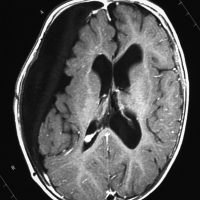

teratomaのparadoxical response

neurohypophyseal mixed germ cell tumorの若年成人男子例です。発症時のMRIでは大部分が増強されますが,腫瘍の右前方に脂肪組織を示す小さな信号域を認めます(上段左の単純MRI,上段右の増強MRI)。経蝶形骨洞生検術でmature teratomaとgerminomaの所見が得られました。ICE化学療法により増強される部分の腫瘍は消失しましたが,逆に下段左の単純MRIと下段中央のCTで認められる脂肪組織を含む部分が顕著に増大しました。この腫瘍は後に亜全摘出しました(下段右)が,病理所見は類皮腫でした。teratomaにおいてはこのような奇異な治療反応性 paradoxical response がみられることがあります。